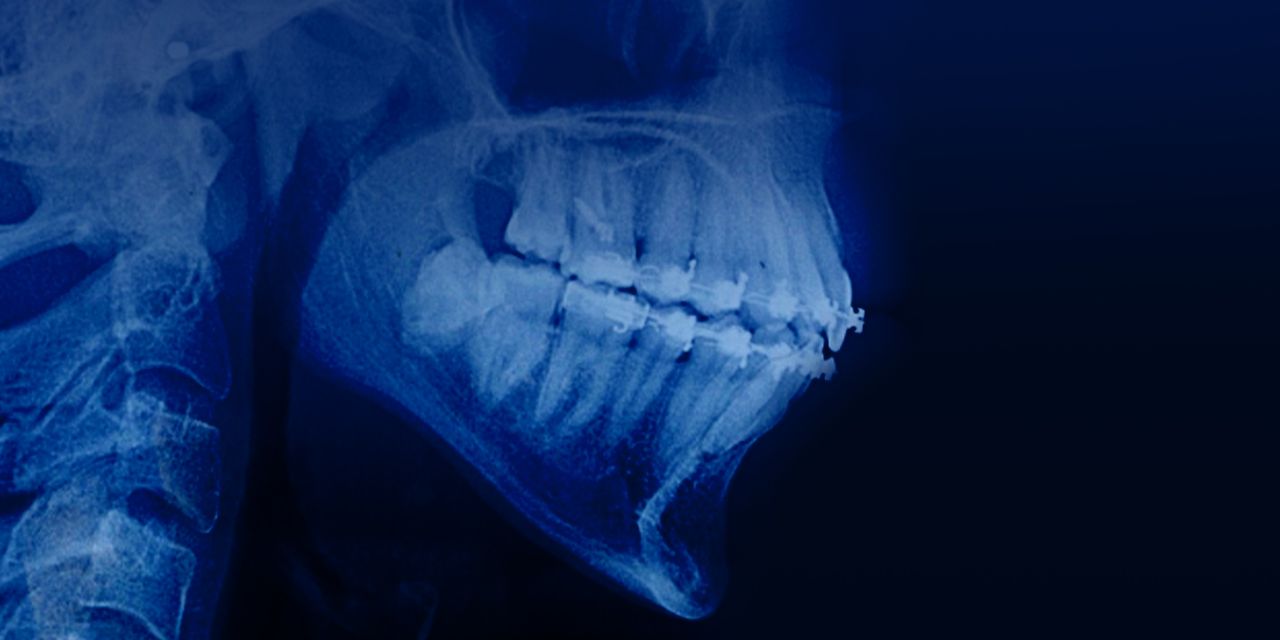

Management of adult patients with open bites & hight mandibular plane angle

– Diagnosis of high mandibular plane angle

– Risks of using transparent aligners in patients with high mandibular plane angle

– Facial morphology: clinical signs of an elongated face

– Etiological factors of high mandibular plane angle and open bite

– Vertical control: meaning and tactics

– Tooth extraction or extrusion: decision-making algorithm

– Indications for tooth extraction

– Biomechanical justifications for the extraction of the 1st, 2nd premolar and 1st molar

– Evaluation of orthodontic treatment of a patient with high mandibular plane angle

– Segmental mechanics: vertical control option

– The effect of stretching transeptal fibers

– Treatment protocol of adult patients with high mandibular plane angle

– Application of microimplants in the lateral segment for intrusion

– Autorotation of mandible

– Surgical intervention: indications.